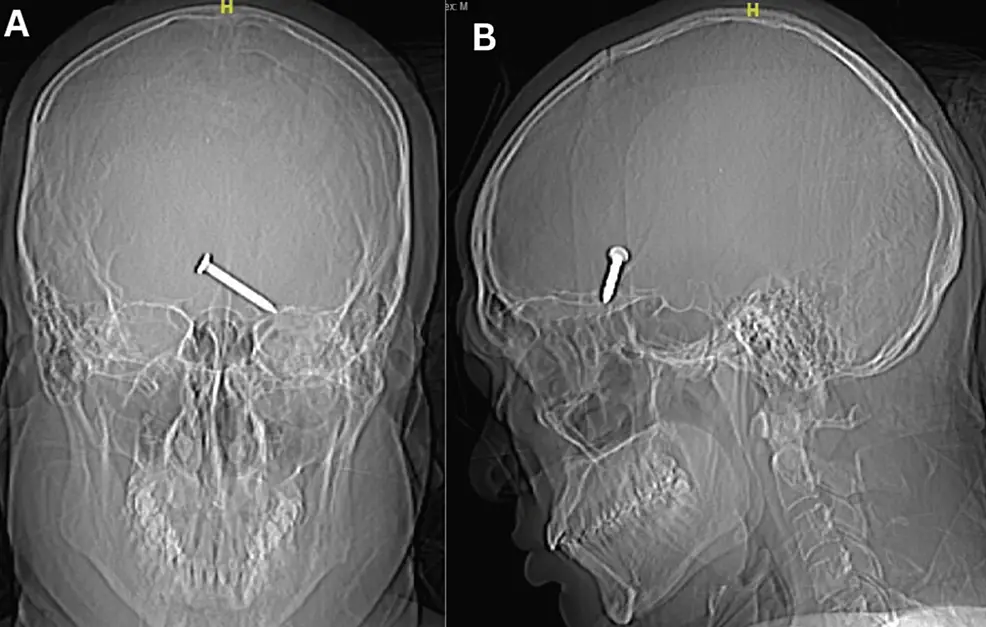

After being examined at hospital Sultanah Bahiyah in Alor Setar he was seen to by stunned doctors. A CT scan showed that the nail had become lodged in the frontal lobe of the brain, the part necessary for movement and language.

In an impressive show of their skills, medics were able to successfully remove the 3.2cm nail in a single piece and there was no active bleeding after removal of the nail.

The nail had managed to miss vital arteries and nerve, suggesting it was unlikely he would suffer from long-term nerve damage.